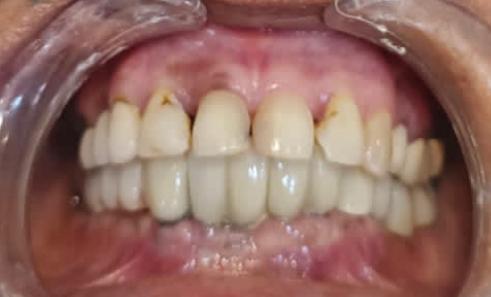

For implant-supported crowns in relation to #18, 19, 20, 21, 22, 23, 24 and 25: The procedure explained to the patient. Consent was taken for cementation of Zirconium implant-supported crown on teeth #18, 19, 20,21,22,23,24, and 25 implant-supported crowns, no anesthesia was given. The temporary crown is taken out, try fitting the crown prior to cementation. Cementation with Fuji 1 Glass Ionomer luting cement. Contoured and checked for high contact with articulating paper and proximal contact with dental floss. Polishing of crown. Post-operative care for crowns was given.

Post-operative clinical picture: Post-op, 6 months: Excellent bone height. Adequate Soft tissue healing